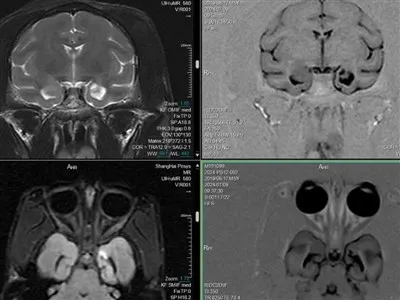

تتضمن نماذج NHP الخاصة بنا نموذج النزيف في الجسم الحي ، ونموذج تحويلة Arterio-Venous (AV) ، ونموذج ركود Wessler ، ونموذج تخثر الشرايين الناجم عن FeCl3. مدة الدراسة القياسية لهذه النماذج هي ساعات ، مع تحديد نقاط نهاية الدراسة من خلال التصميم التجريبي المحدد. تشمل نقاط النهاية السريرية وقت النزيف / الوزن ، ووزن الجلطة / الجلطة ، واختبارات التخثر ، وسرعة تدفق الدم ، وتصوير التخثر.

تم تصميم نماذجنا لتوفير تقييمات شاملة للإرقاء ، وتقييمات السلامة ، ودراسات مضادة للتخثر ، ودراسات عوامل التخثر ، وتقييمات التخثر داخل الحجاج. تمكننا هذه النماذج من اكتساب فهم أعمق للآليات الأساسية للتخثر والتخثر ، وتوفر أداة قوية لتطوير واختبار علاجات جديدة لأمراض الأوعية الدموية.